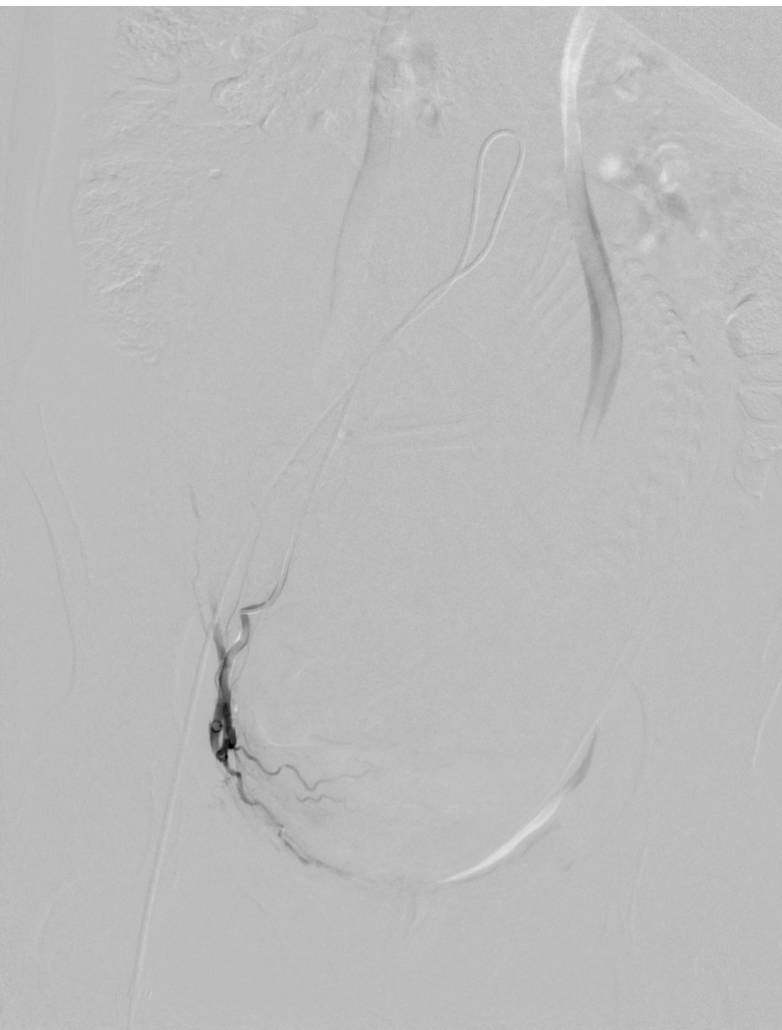

在DSA下能清楚的看到子宫中胎儿的形状(脊柱、颅脑、四肢),还不停的在胎动。介入治疗用明胶海绵栓塞双侧子宫动脉减少子宫的供血图一(左侧子宫动脉栓塞前后,右侧同左侧)。

图一:左侧子宫动脉栓塞前

图一:左侧子宫动脉栓塞后